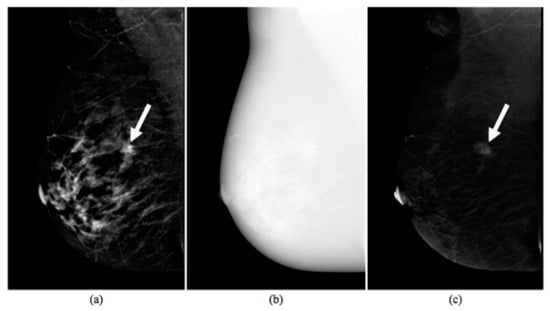

An example of CESM images is shown in Figure 1, which includes a LE image (a), a HE image (b) and their RC image (c).

Figure 1. Images produced by contrast-enhanced spectral mammography (CESM instrumentation). Typical example of low energy (a), high energy (b), and recombined (c) images [17]. The white arrow points out a suspicious lesion.